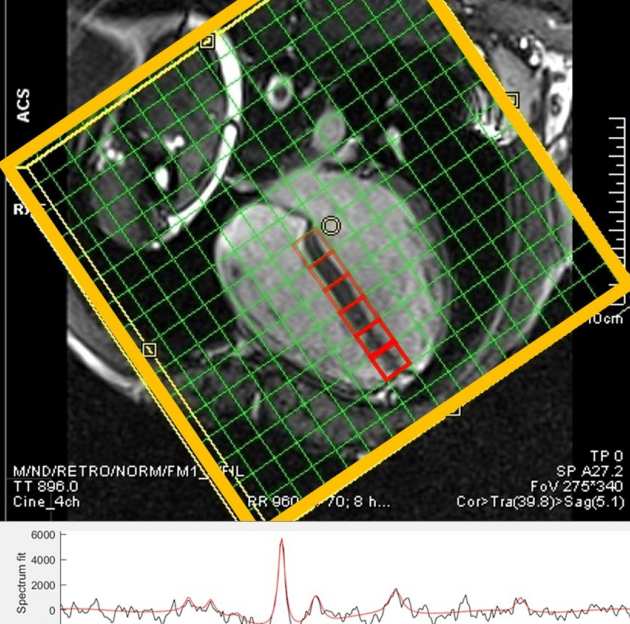

31P MRS

We are using 31P MRS to explore variations in cardiac muscle composition and function in a population cohort with genetic and phenotypic variants associated with cardiovascular disease.

We are using 31P MRS to explore variations in cardiac muscle composition and function in a population cohort with genetic and phenotypic variants associated with cardiovascular disease.